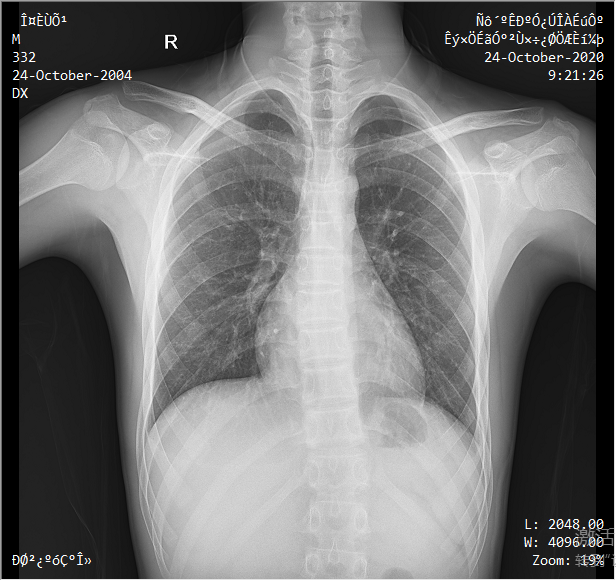

采用靈活的懸吊式機架設計,配置電動升降攝影床/移動床與高品質平板探測器,實現圖像與擺位的有機統一,可應用于DR攝影多種臨床X線檢查領域。

● 3D擺位指示

醫生選擇需要拍攝的部位,自動生成擺位示意圖像,引導病人快速準確的完成擺位。